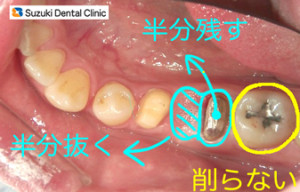

歯を出来るだけ残す取り組み

コラム「歯を出来るだけ残す取り組み」の画像